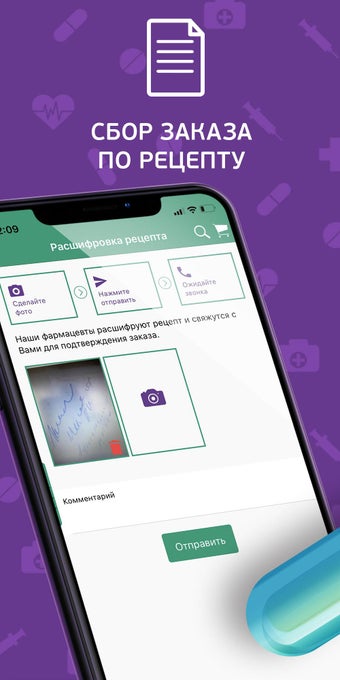

Với vài cú nhấp chuột, bạn có thể mua bất kỳ loại thuốc nào bạn cần cho bản thân hoặc gia đình của mình, bất kể loại thuốc đó.

Bạn có thể sử dụng ứng dụng để tìm kiếm các loại thuốc không có sẵn trong nhà thuốc của bạn, đặt hàng giao hàng đến nhà của bạn hoặc đặt hàng từ một nhà thuốc gần bạn.